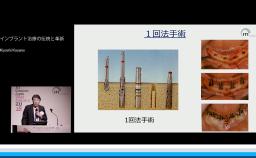

本講演では,上顎洞底挙上術の一手法である側方開窓術の術前臨床的判断基準,術式詳細,臨床経過,CBCT所見,術後偶発症,文献的考察から,開窓部へのバリアメンブレン設置を整理する.

上顎洞底挙上術(術式や合併症など)の理論が理解できる。